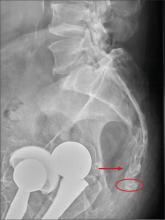

A 75-year-old man presents to the urgent care center for evaluation of pain in his buttocks after a fall. He states he was walking when his “legs gave out” and he hit the ground. He landed squarely on his buttocks, causing immediate pain. He was eventually able to get up with some assistance. He denies any current weakness or any bowel or bladder complaints. His medical/surgical history is significant for coronary artery disease, hypertension, and bilateral hip replacements. Physical exam reveals an elderly male who is uncomfortable but in no obvious distress. His vital signs are stable. He has moderate point tenderness over his sacrum but is able to move all his extremities well, with normal strength. Radiograph of his sacrum/coccyx is shown. What is your impression?

There are degenerative changes present. Bilateral hip prostheses are noted. Within the coccyx, there is bone remodeling and angulation that are likely chronic and related to remote trauma or injury (arrow). Below this, some cortical lucency (circled) is noted, most likely consistent with an acute fracture. The patient was prescribed a nonsteroidal medication and a mild narcotic pain medication.